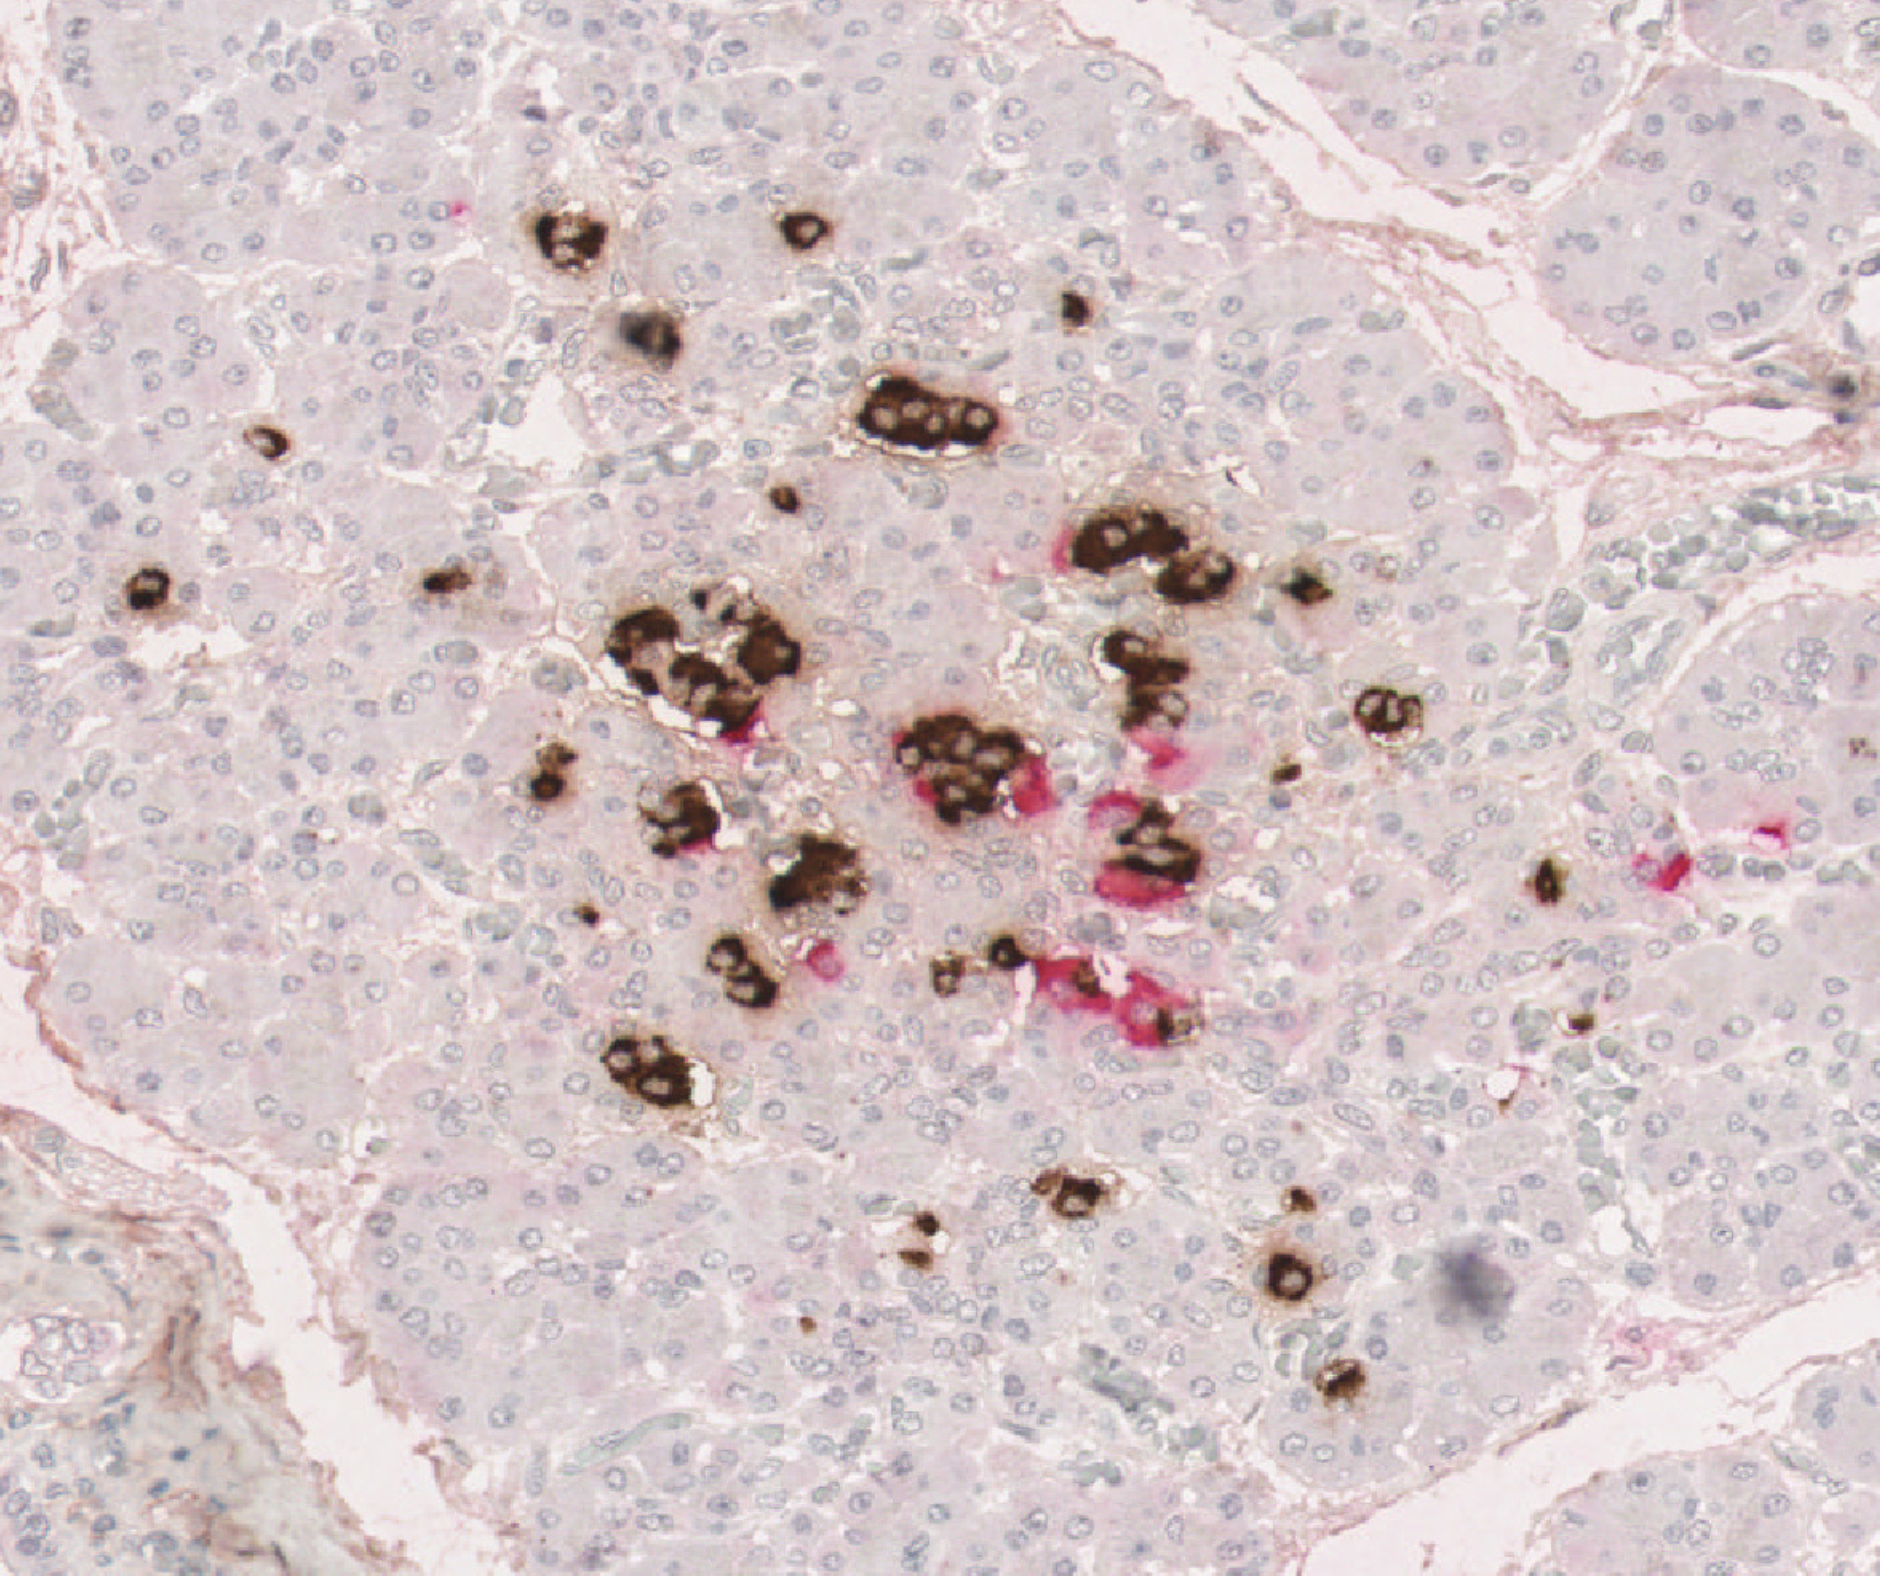

In their latest study published in Science Advances, Professor Richardson and her team used cutting-edge scientific techniques to study these small clusters in unprecedented detail. They analysed rare pancreas samples from over 250 people of varying ages, both with and without type 1 diabetes. They looked at how these clusters change as we age and how they are affected by the immune system.

The findings confirm that in early childhood, people without type 1 diabetes have many small clusters of beta cells, which normally increase in size and mature with age, with the most rapid development occurring in the first few years of life.

For the first time, our Grand Challenge researchers showed that in people with type 1 diabetes these small clusters are almost completely absent, having been destroyed by the immune system. While some people with type 1 diabetes retained a few large clusters, allowing them to produce small amounts of their own insulin, this was not the case for those diagnosed at a young age.

Together, the results suggest that the abundant small clusters found in young children are especially vulnerable to the type 1 diabetes immune attack. Their rapid destruction prevents them from maturing, leaving very few beta cells later in life. This explains why children diagnosed with type 1 diabetes at a young age typically are unable to produce any of their own insulin, making the condition particularly difficult to manage.